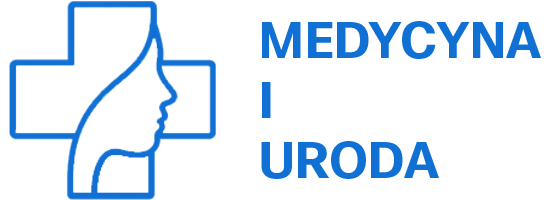

Najczęściej ropień zęba występuje u osób w wieku 16–34 lat (52%), rzadziej u pacjentów w wieku 35–59 lat (41%) i bardzo rzadko u osób starszych, w wieku 60–74 lat (7%). W 79% przypadków pacjenci zgłaszają się do lekarza dopiero między 5. a 10. dniem od początku choroby. Hospitalizacja w pierwszych 2–4 dniach jest konieczna jedynie u 21% pacjentów. Najczęściej przyczyną ropnia są zęby żuchwy (72%), rzadziej zęby szczęki (28%). Ropień częściej powstaje przy trzonowcach niż przy przedtrzonowcach.